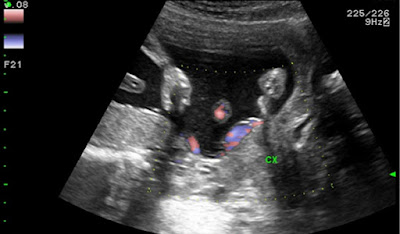

經陰道超音波檢查,B-mode (圖1a)及Color Doppler (圖1b),可發現Color Doppler的確有助於辨識位於子宮頸內口前方的血管。

在第二孕期常規經陰道測量子宮頸長度的同時輔以Color Doppler篩檢前置血管,若觀察到疑似前置血管情形但又無法明確判斷該血管為母體血管或胎兒臍帶時,再以Pulse-wave Doppler鑑別。產前是否正確診斷前置血管,對於新生兒的預後有關鍵性的影響,產前正確診斷前置血管並給予適時的剖腹產,新生兒存活率可達96.7%, 反之新生兒存活率則僅43.6% (Obstet Gynecol 2004;103:937-42)。Ultrasound Obstet Gynecol 2015;45:516–522對於在不同孕期,經陰道或經腹部超音波產前診斷前置血管的準確率做了詳細的系統性分析,發現最常診斷前置血管的懷孕週數是18到26週,經陰道超音波加上Color Doppler的診斷方式的確可以獲得最高的診斷準確率(90-100%)。